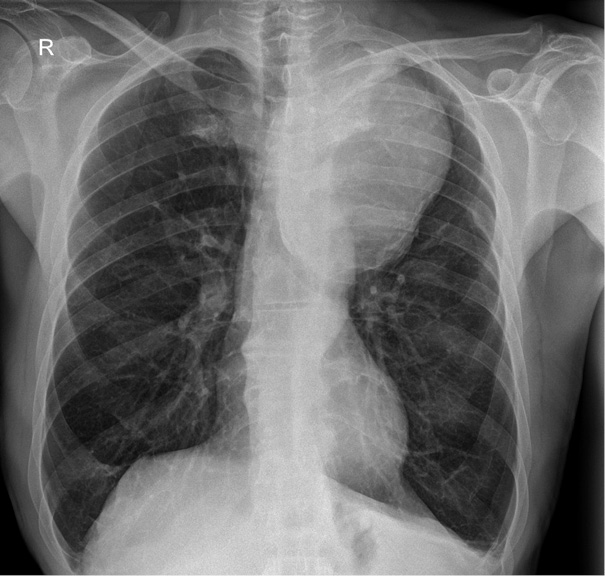

The detection of a mediastinal mass prompted differential diagnostic considerations, primarily focusing on two major possibilities: (1) mediastinal tumor formation associated with lymphocytic infiltration due to leukemia or other oncological masses, and (2) a giant vascular aneurysm. To delineate the etiology, a two-dimensional CT scan of the thoracic aorta was performed, as shown in Figure 2, revealing a large aneurysm in the distal post-arch segment of the descending aorta. The observed mass corresponds to a giant aneurysmal dilation.

The aneurysm measured 14.08 × 10.04 cm in its maximum transverse diameters. No chronic thrombus was identified within the tunica media, nor was there any evidence of dissection. The proximal ascending aorta measured 38 mm in diameter. Figure 3, which depicts a three-dimensional CT reconstruction, delineates the anatomical relationship of the aneurysm with the aortic arch, the left subclavian artery, and the descending thoracic aorta. The aneurysm was localized, with no involvement of the proximal left subclavian artery or its orifice. The distal portion of the aneurysm did not extend to spinal or intercostal branches. The remainder of the aorta, including the abdominal segment, appeared normal. The primary clinical impact of the aneurysm was attributed to a significant mass effect, leading to compression of the trachea and bronchi as well as potential irritation of the left phrenic nerve secondary to mediastinal compression.

GDTAA often presents with non-specific symptoms that are primarily due to mass effect rather than rupture [19]. Common clinical manifestations include dyspnoea, cough, chest pain and dysphagia due to compression of adjacent structures such as the trachea, bronchi and oesophagus [9]. In the case presented, the patient had recurrent syncope, persistent cough and fatigue, which correlated with significant deviation of the trachea and compression of the airway structures on imaging [20].

CT angiography remains the gold standard for the diagnosis and assessment of the extent of GDTAA [21]. It allows high-resolution visualisation of the size and morphology of the aneurysm as well as the anatomical relationships with the adjacent structures [21]. In this case, CT imaging confirmed a massive aneurysm with significant displacement of the trachea and compression of the bronchi, thereby emphasising the crucial role of modern imaging in surgical planning [21].